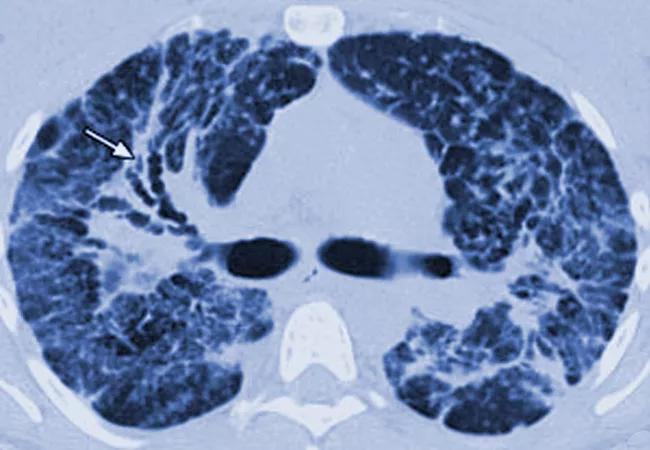

Imaging in sarcoidosis

Mild symptoms and a quick recovery are common in most cases of sarcoidosis, but a minority of patients have significant morbidity and impaired quality of life (QoL) because of multiorgan involvement. Patient income may be a key factor in the poorer disease outcomes, according to results of a new study led by Cleveland Clinic researchers.